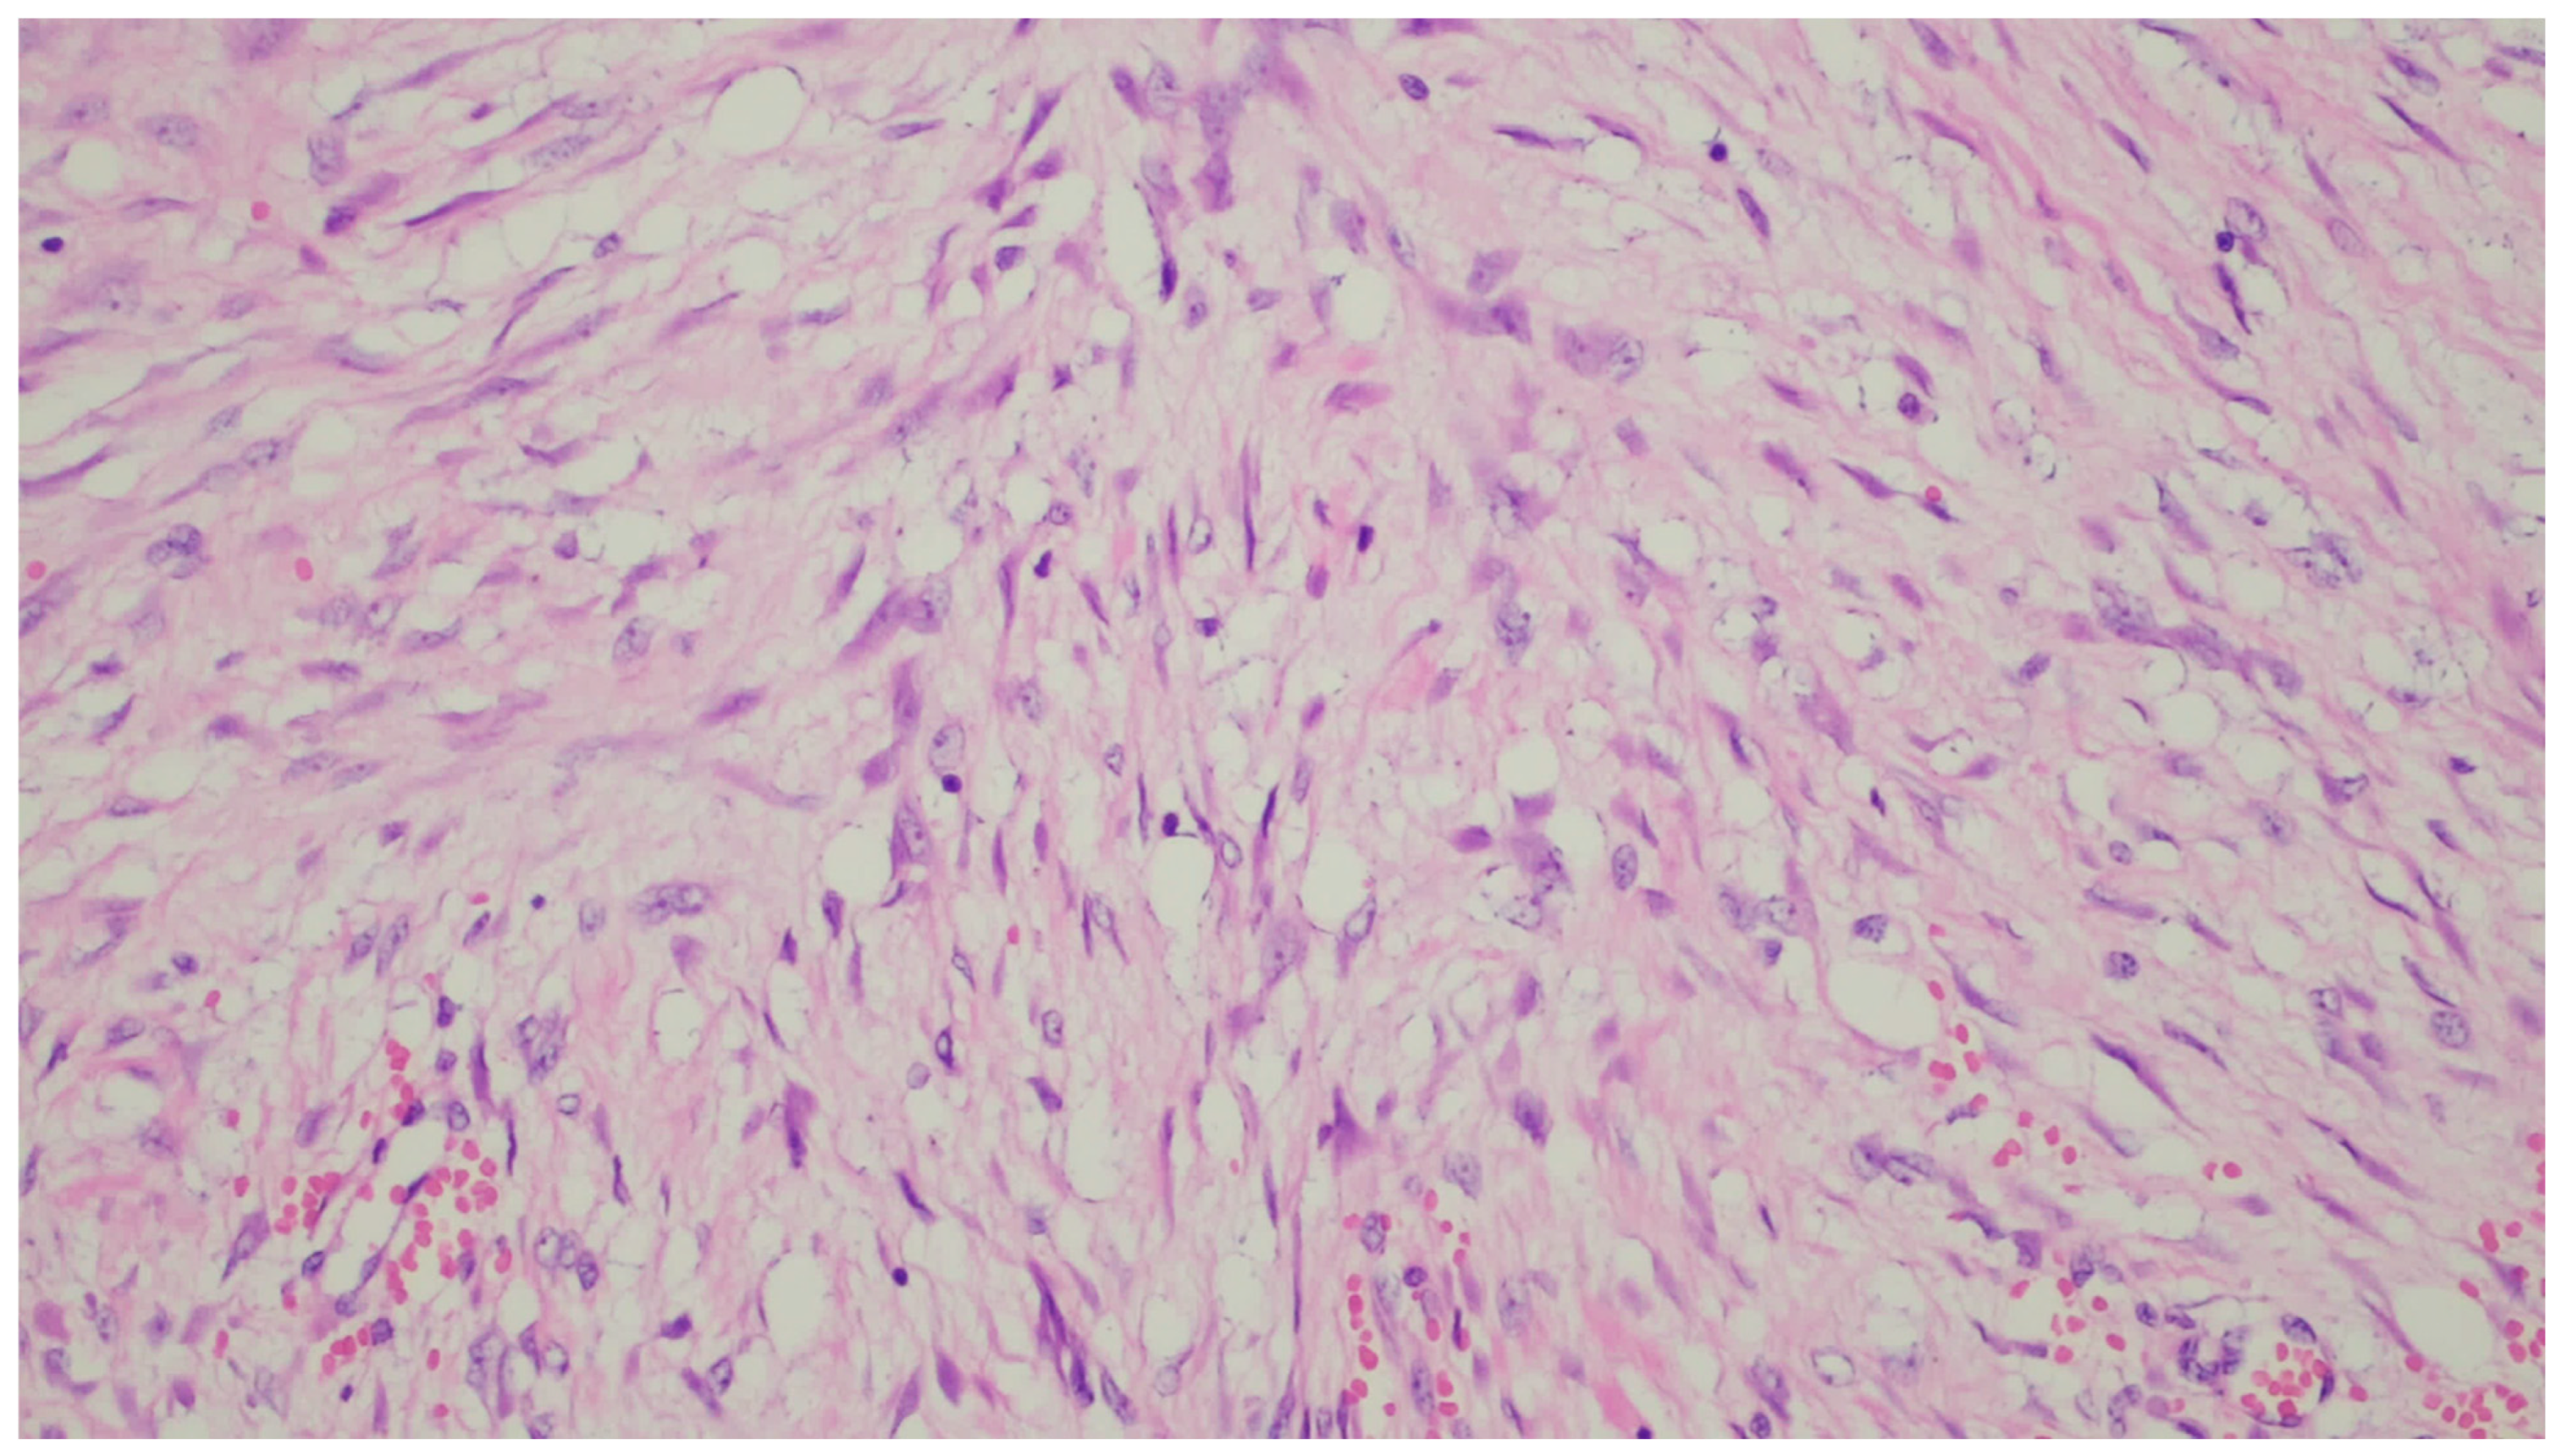

| Plexiform fibromyxoma | Wide range of age | Antrum and pyloric region | Asymptomatic; some cases with ulceration | Bland spindle cells, supported by a myxoid/fibromyxoid/collagenous stroma and with a rich vascular network of thin-walled vessels in a multinodular pattern | SMA and, occasionally desmin positive. ALK, CD34, keratins, KIT, and DOG1 are negative |